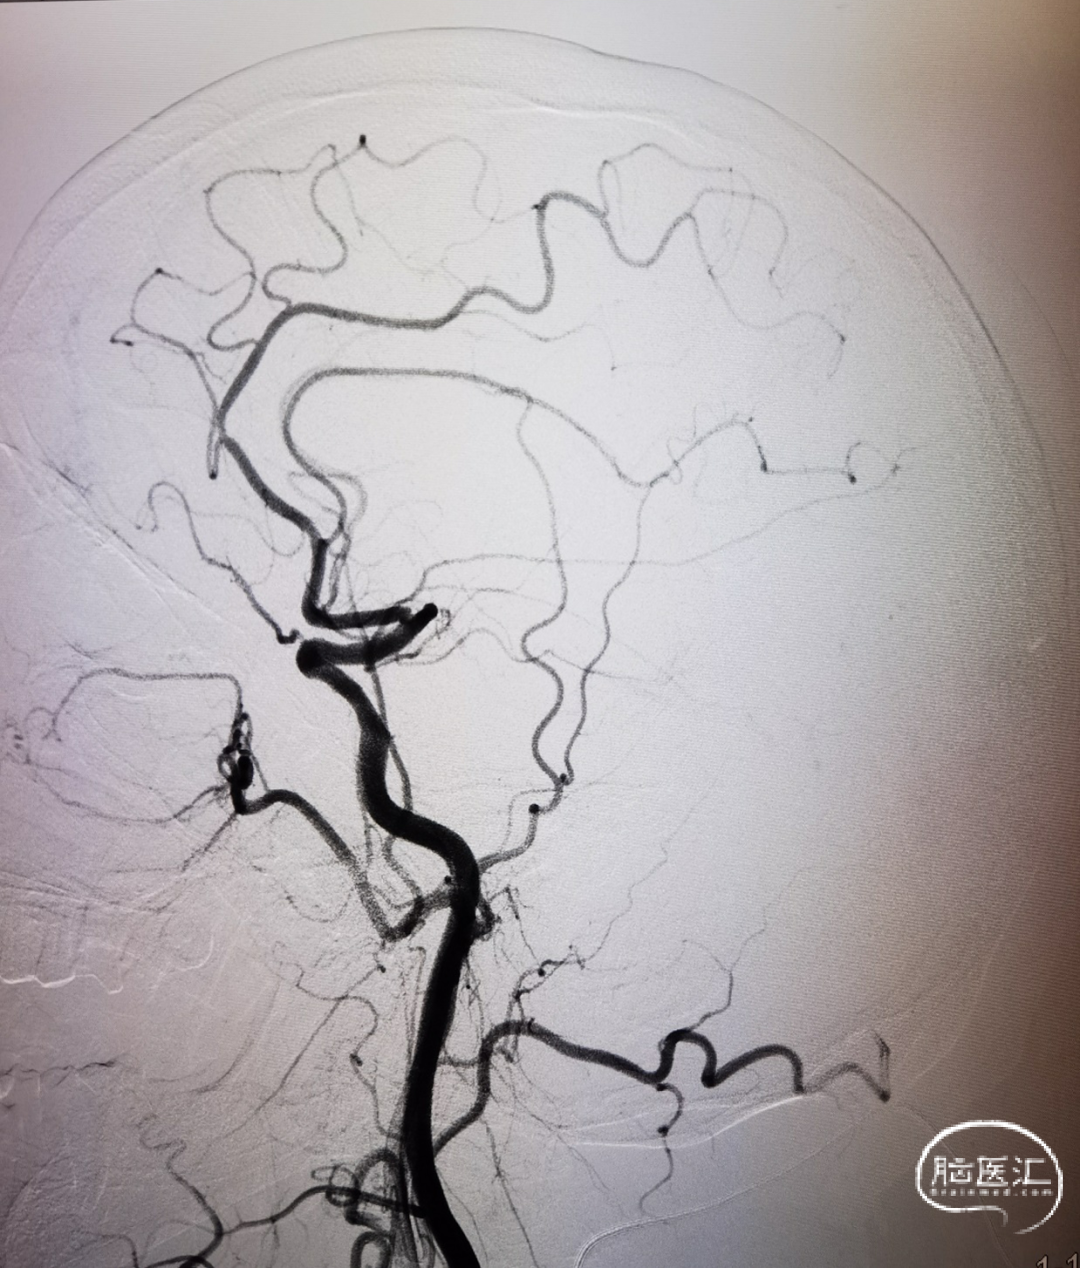

造影证实左侧大脑中动脉M1段闭塞。

构建治疗通路,微导管穿过闭塞段后造影确认真腔,置入Syphonet®取栓支架,支架通体显影,提供良好的视觉反馈,全程可视化操作。

首过效应阳性。

球囊泄压后利用Syphonet®取栓支架的锚定效果让中间导管靠近闭塞段;撤出快交球囊后采用SWIM技术取栓;术后造影证实血管再通。

开通后血流再次闭塞,考虑球扩后夹层形成可能;补救性予以电解脱释放Solitarie支架后正侧位造影。